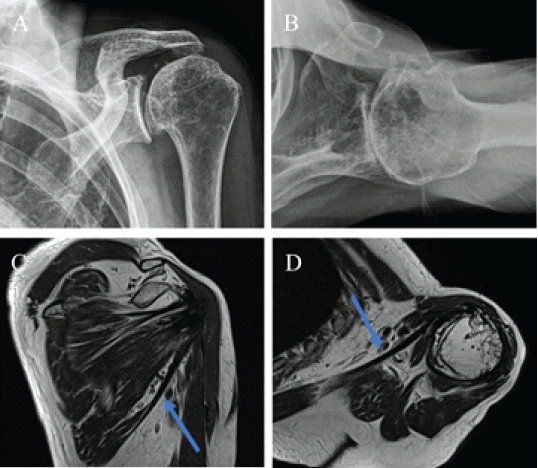

Over time, she experienced worsening pain and functional limitations, particularly during daily tasks such as food preparation, toileting, and personal hygiene, which significantly reduced her quality of life. Clinical evaluation demonstrated FE of 130°, abduction of 130°, external rotation (ER) of 40°, and IR to the L3 vertebral level. Strength testing showed values of 20.1 N for FE, 24.3 N for abduction, 22.7 N for ER, and 27.9 N for IR. Patient-reported outcomes indicated moderate disability, with a visual analogue scale (VAS) score of 6/10, a constant score of 56/100, and the American Shoulder and Elbow Surgeons (ASES) score of 59/100. Radiographs revealed advanced glenohumeral osteoarthritis with joint space narrowing and superior migration of the humeral head. Magnetic resonance imaging demonstrated humeral head cartilage loss, glenoid wear, and an intact, well-preserved latissimus dorsi transfer (Fig. 2). Considering the severity of osteoarthritis and persistent symptoms, rTSA was performed with preservation of the prior LDT.

Figure 2: Radiographs and magnetic resonance imaging 10 years after anterior latissimus dorsi tendon transfer. (a) Anteroposterior and (b) axil radiograph of left shoulder demonstrating advanced glenohumeral osteoarthritis with joint space narrowing and superior migration of the humeral head. (c) Coronal and (d) axial T2-weighted magnetic resonance image showing well-preserved transferred latissimus dorsi tendon attached to the lesser tuberosity.